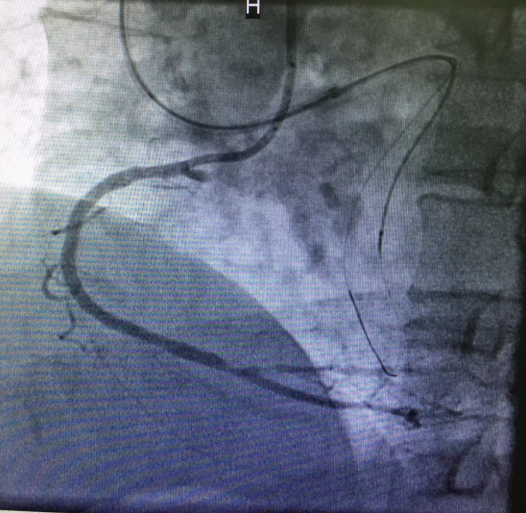

心内三完成21点游戏攻略站 首例逆向开通冠脉CTO病变